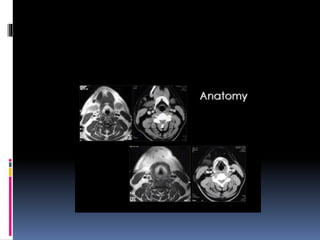

 Coronal sections of the nasopharynx show the-

eustachian tube opening, torus tubaris. Fossa of

rosenmuller and the adenoids, if present.

 Asymmetry of the Fossa of rosenmuller should

be looked for.